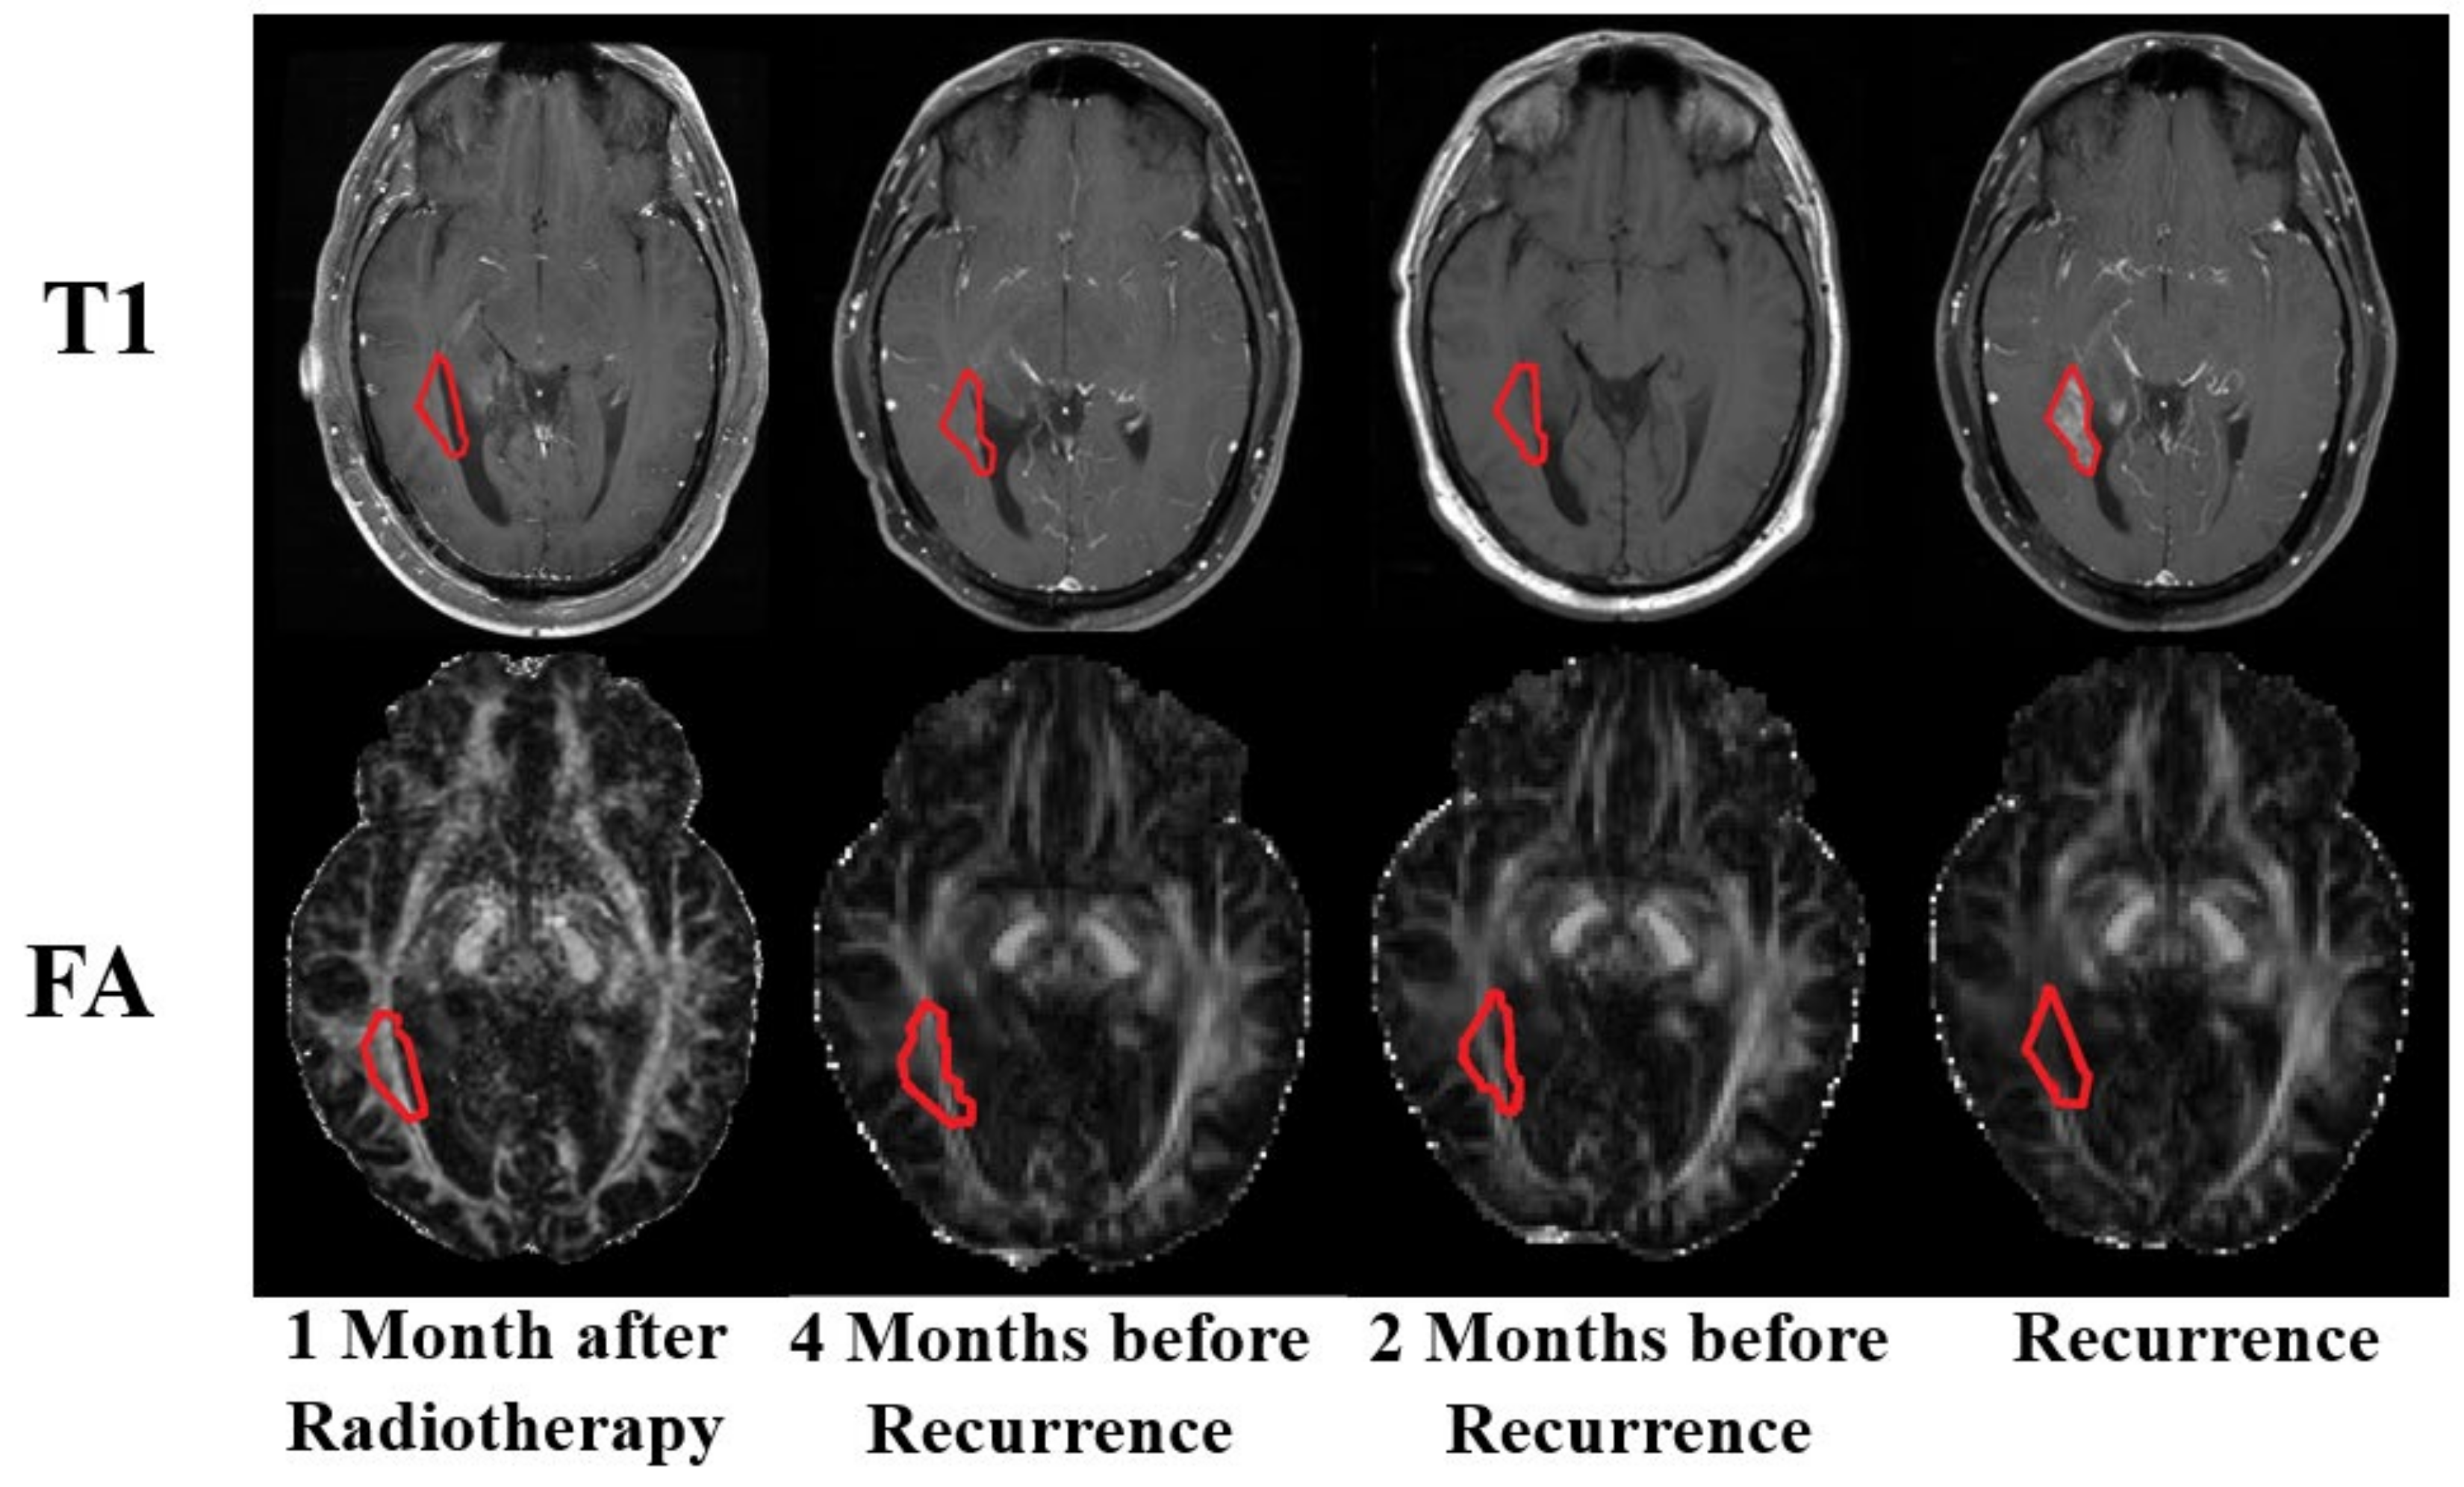

3.3. Qualitative Comparison

3.4. Radiation Therapy versus Recurrence